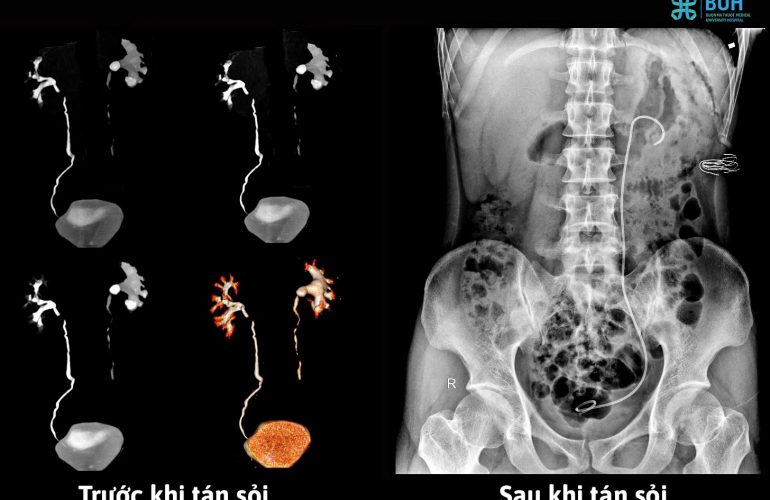

ĐIỀU TRỊ SỎI THẬN AN TOÀN – HIỆU QUẢ VỚI CHI PHÍ HỢP LÝ TẠI BUH

Sỏi thận là căn bệnh thường…